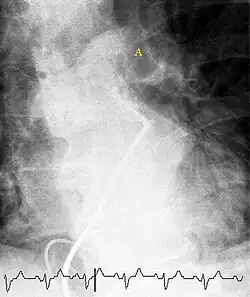

Selective pulmonary angiogram revealing significant thrombus (labelled A) causing a central obstruction in the left main pulmonary artery

Pulmonary angiography (or pulmonary arteriography,conventional pulmonary angiography, selective pulmonary angiography) is a medical fluoroscopic procedure used to visualize the pulmonary arteries and much less frequently, the pulmonary veins. It is a minimally invasive procedure performed most frequently by an interventional radiologist or interventional cardiologist to visualise the arteries of the lungs.

Pulmonary angiography is useful as the confirmation test where the non-invasive imaging such as CT pulmonary angiography is inconclusive on determining the presence of pulmonary embolism.[1] The accuracy of pulmonary angiography may be higher than clinical examination, arterial blood gas results, and ventilation/perfusion scan.[2] Pulmonary angiography is also used to confirm chronic thromboembolic pulmonary hypertension (CTEPH) and provides a platform for balloon pulmonary angioplasty to treat the disease.[3]